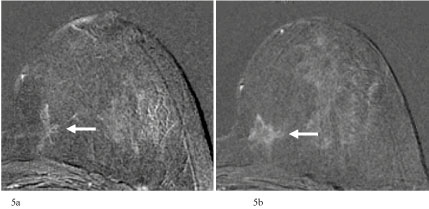

The size of the detected invasive breast carcinomas ranged from 2 to 22 mm in this study. The greater proportion detected by MRI at a size of more than 15 mm within 2 years after an inconspicious MRI exam were lobular (4 of 7 breast carcinomas; 57%). The reason for this is the indian-file growth pattern of lobular breast cancers, resulting in large tumor sizes with a low count of tumor cells in comparison to the solid growth type of ductal carcinomas (Figure 5a and Figure 5b). In this context it could be considered whether the metric of a tumor in millimeters is an optimal criterion for the assessment of invasive lobular carcinomas. There are, however, also invasive ductal carcinoma that increase in size to 15 mm or more within an intervall of 1-2 years. In the presented study, all of the detected invasive ductal carcinomas of 15 mm or larger were tumors of grading 3 (Figure 6a and Figure 6b). In summary, the detection of breast cancer at a stage of pT2 or higher is rare if MRI is performed at intervals of 24 months or less. In the presented study, this rate was 1.3% of all invasive carcinomas.

Figure 5: a) 56-year-old patient with moderate increased life time risk. In the single-slice subtraction stellate non-mass-like lesion in the inner part of the left breast. Changes were (mis)interpreted as parenchymal enhancement. Categorization: MR-BIRADS left breast 1. Next MRI was recommended in 18 months; b) MRI of the breast 19 months later. Single-slice subtraction image shows an increase of the size of the non-mass-like lesion in the inner quadrant of the left breast to more than 20 mm. Categorization: MR-BIRADS left breast 4. No corresponding findings in mammography (MX-BIRADS 1), but suspicious architectorial distorsion in ultrasound (US-BIRADS 4). US-guided core biopsy: B5b. Final histology: Invasive lobular carcinoma, pT1c (22 mm), grading 2, Luminal A, pN0. View Figure 5